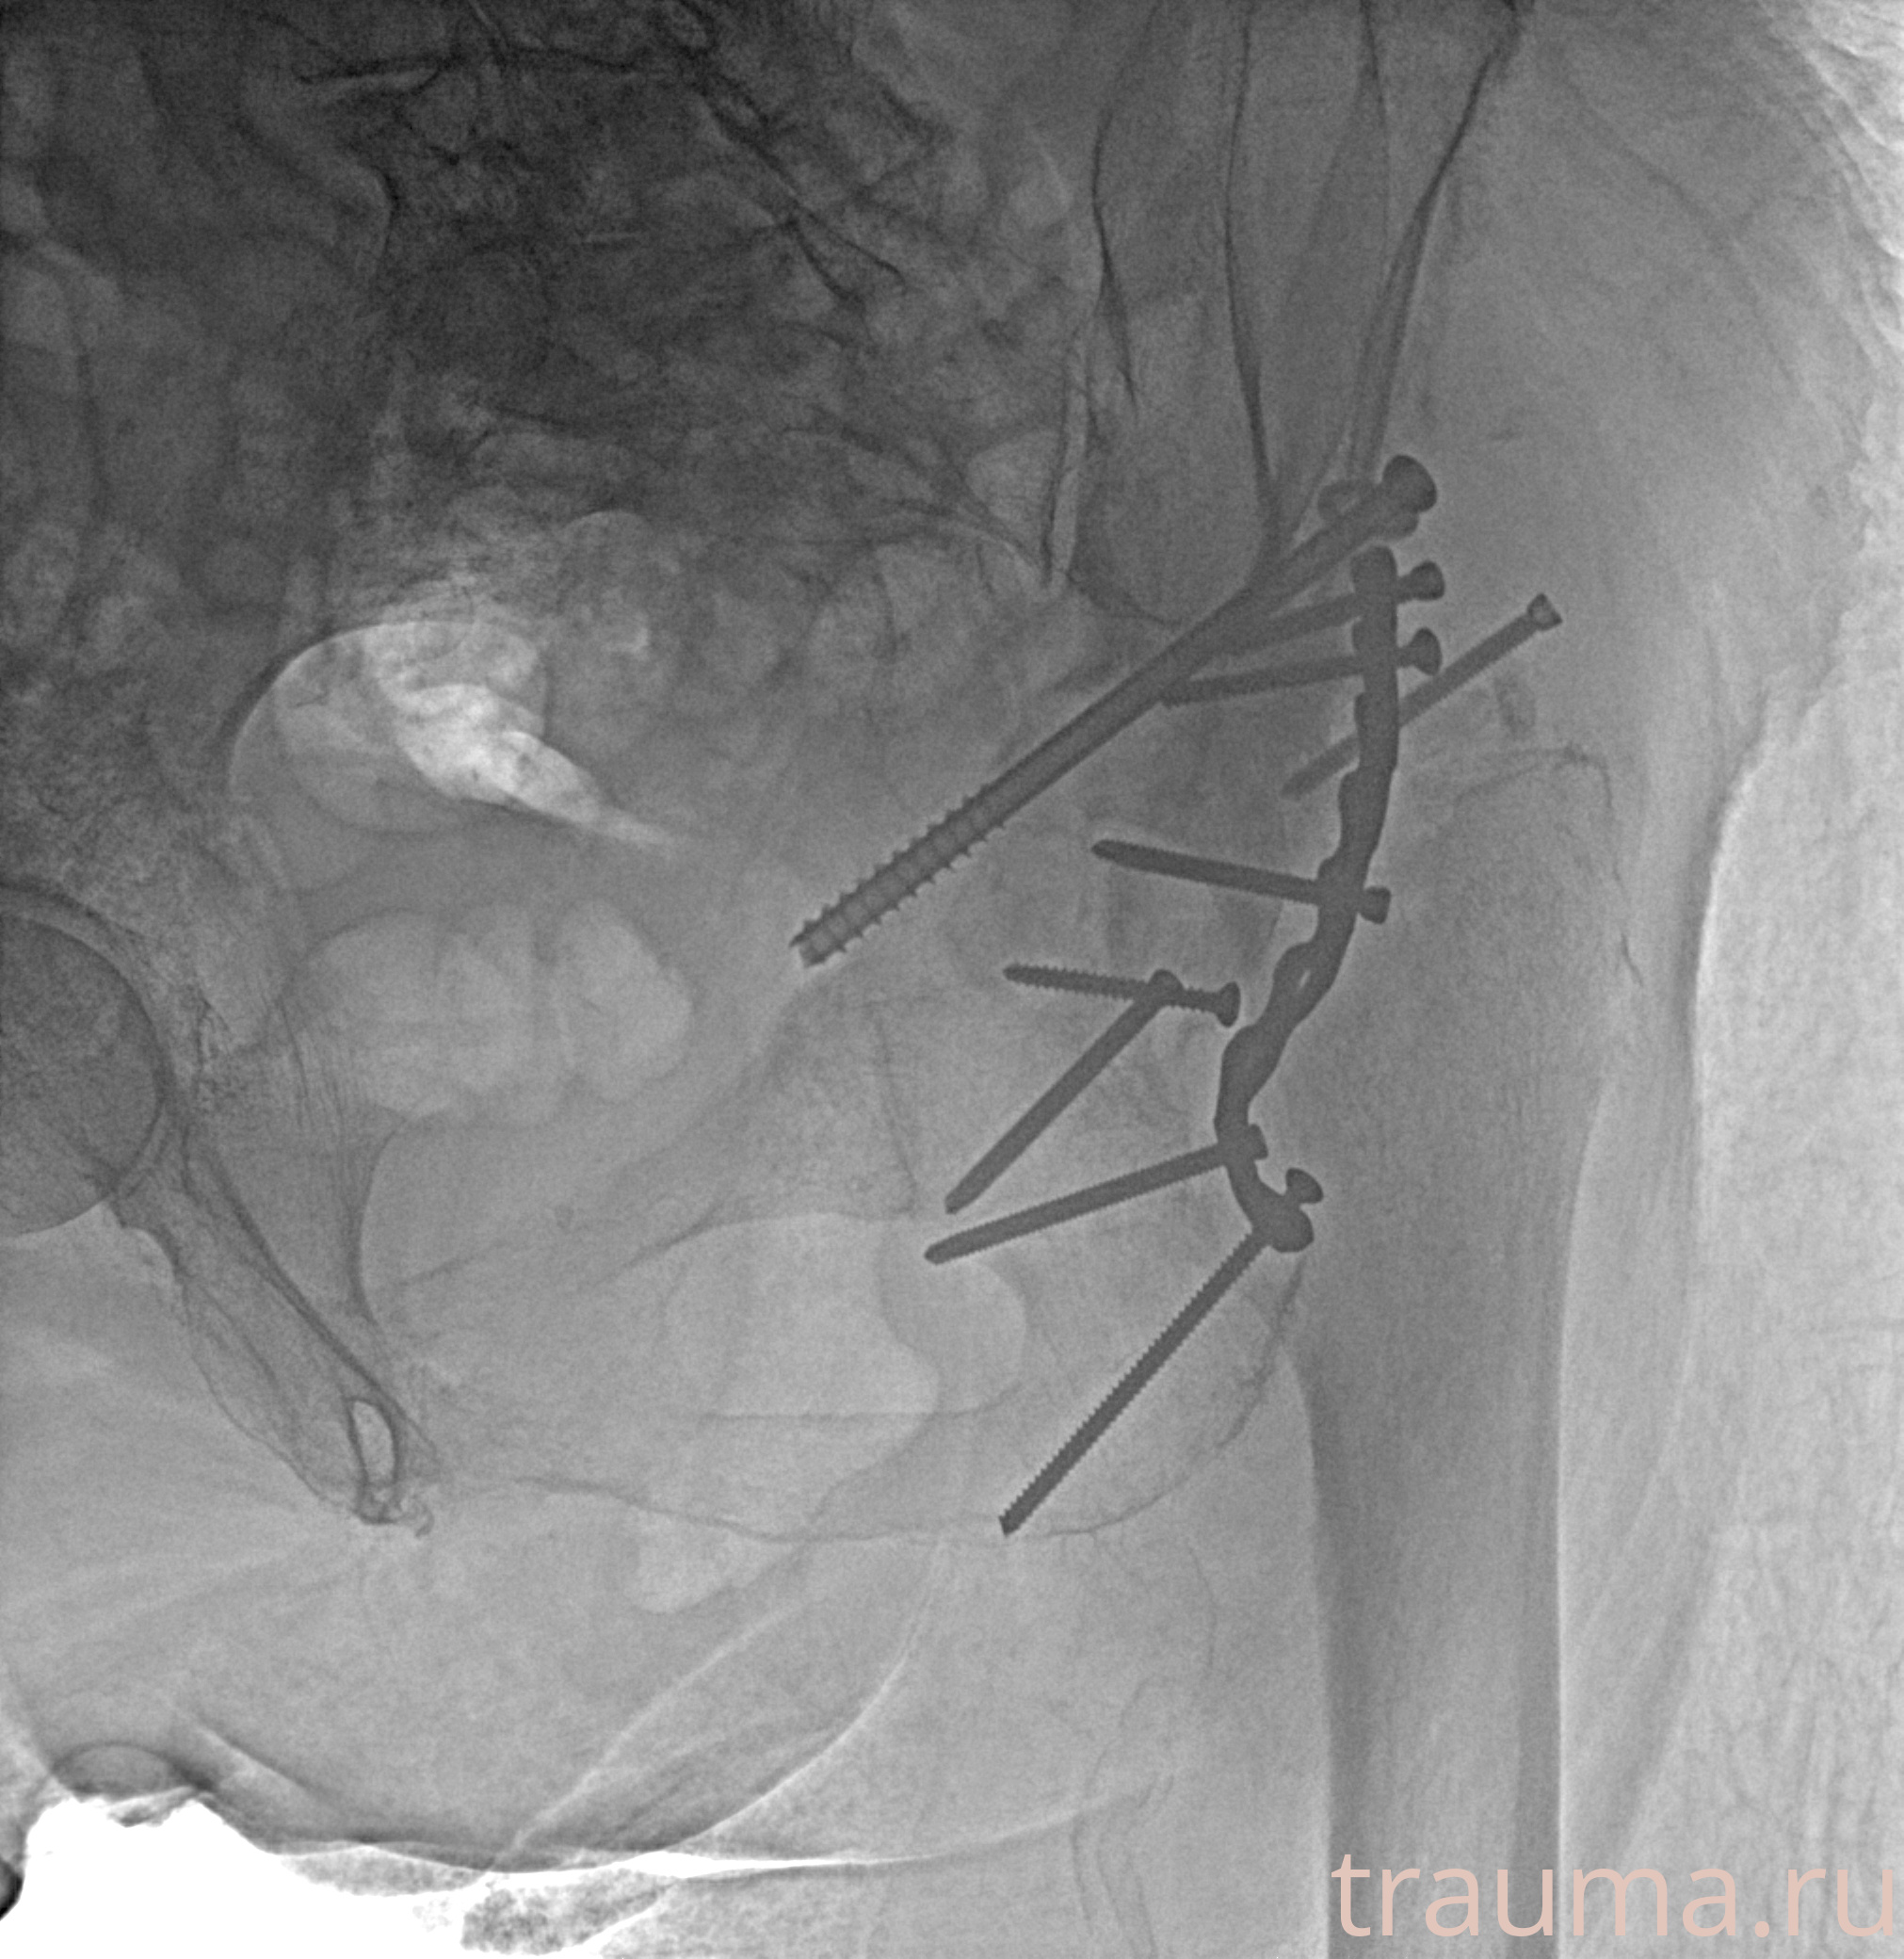

Рентгенограммы

Рентген на дому: по вашему адресу приезжает врач-рентгенолог, травматолог-ортопед с мобильным рентгеновским аппаратом, проводит диагностику травмы или заболевания, делает необходимые рентгенограммы, дает рекомендации по дальнейшему лечению. Получить качественные снимки в домашних условиях возможно благодаря уникальной методике, разработанной МосРентген Центром для института  Склифосовского